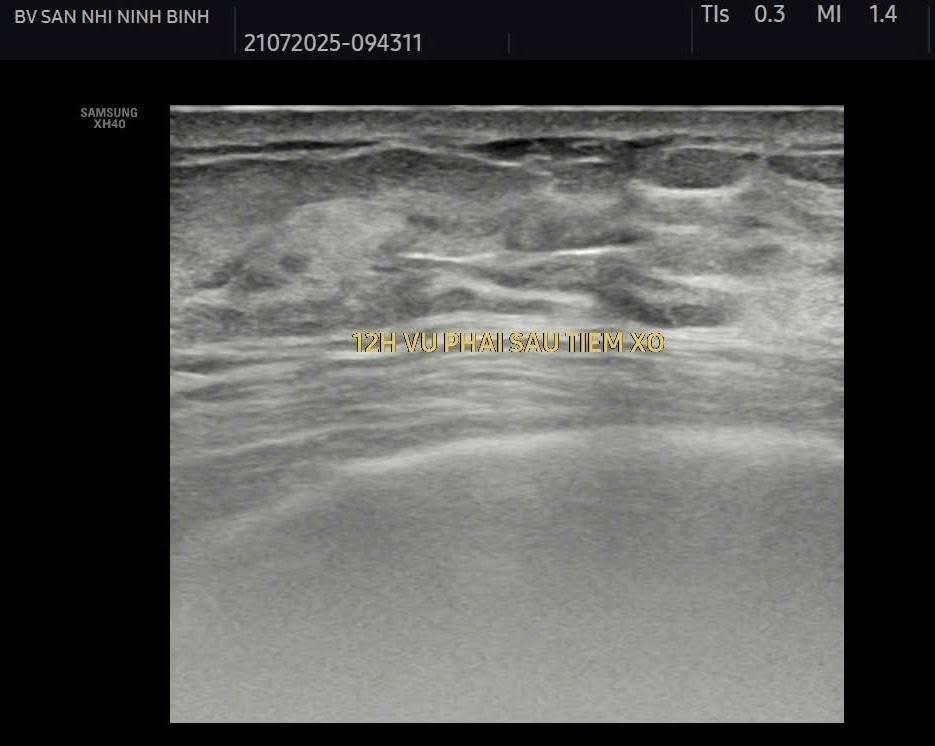

Điều trị diệt nang vú bằng các phương pháp can thiệp tối thiểu như tiêm cồn hoặc các chất gây xơ hóa sau chọc hút nang là phương pháp ít xâm lấn và tỷ lệ tái phát thấp.

Hiện bệnh viện Sản Nhi Ninh Bình đã thực hiện phương pháp điều trị tiêm xơ nang tuyến vú dưới hướng dẫn siêu âm, thực hiện nhanh chóng, thuận tiện ngay tại khoa Chẩn đoán hình ảnh. Giúp bệnh nhân điều trị hiệu quả, tránh tái phát, không cần vào viện và theo dõi tại nhà dưới sự hướng dẫn, dặn dò kĩ càng của bác sỹ điều trị trực tiếp.